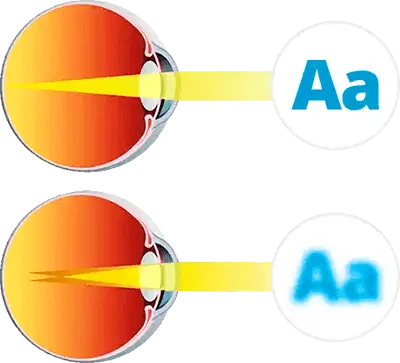

- Los problemas de refracción y la visión borrosa tienen un gran impacto en las actividades diarias.

- El daño en el sistema muscular que enfoca los ojos hace que la imagen que pasa por el cristalino se proyecte incorrectamente sobre la retina.

- La inflamación provoca fatiga ocular y aumenta el riesgo de queratitis.